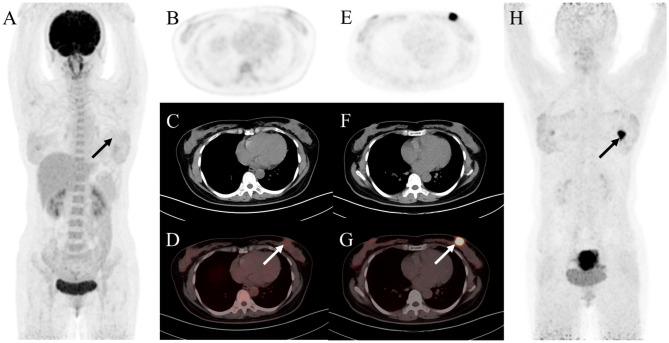

Ga-FAPI (fibroblast activation protein inhibitor) is a novel and highly promising radiotracer for PET/CT imaging. It has shown significant tumor uptake and high sensitivity in lesion detection across a range of cancer types. We aimed to compare the diagnostic value of Ga-FAPI and F-FDG PET/CT in common gynecological malignancies.

Thirty-five patients (median age, 57 years [interquartile range], 51-65 years) were evaluated. In treatment-naive patients (n = 27), Ga-FAPI PET/CT led to upstaging of the clinical TNM stage in five (19%) patients compared with F-FDG PET/CT. No significant difference in tracer uptake was observed between F-FDG and Ga-FAPI for primary lesions: breast cancer (7.2 vs. 4.9, P = 0.086), ovarian cancer (16.3 vs. 15.7, P = 0.345), and cervical cancer (18.3 vs. 17.1, P = 0.703). For involved lymph nodes, Ga-FAPI PET/CT demonstrated a higher SUV for breast cancer (9.9 vs. 6.1, P = 0.007) and cervical cancer (6.3 vs. 4.8, P = 0.048), while no significant difference was noted for ovarian cancer (7.0 vs. 5.9, P = 0.179). Furthermore, Ga-FAPI PET/CT demonstrated higher specificity and accuracy compared to F-FDG PET/CT for detecting metastatic lymph nodes (100% vs. 66%, P < 0.001; 94% vs. 80%, P < 0.001). In contrast, sensitivity did not differ significantly (97% vs. 86%, P = 0.125). For most distant metastases, Ga-FAPI exhibited a higher SUV than F-FDG in bone metastases (12.9 vs. 4.9, P = 0.036).

Ga-FAPI PET/CT demonstrated higher tracer uptake and was superior to F-FDG PET/CT in detecting primary and metastatic lesions in patients with common gynecological malignancies.